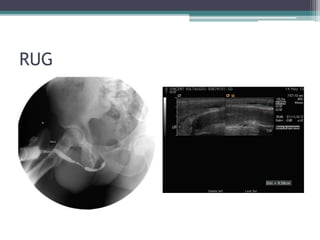

Case #4

โ€ข 56 M with BPH, underwent TURP and now

with post-op LUTS.

โ–ซ Uroflowmetry โ€“ max flow rate 5.5 mL/sec,

obstructive pattern

โ–ซ Cystoscopy โ€“ narrowing at penoscrotal

junction, unable to pass cystoscope

โ–ซ SP tube placed

โ–ซ RUG

RUG